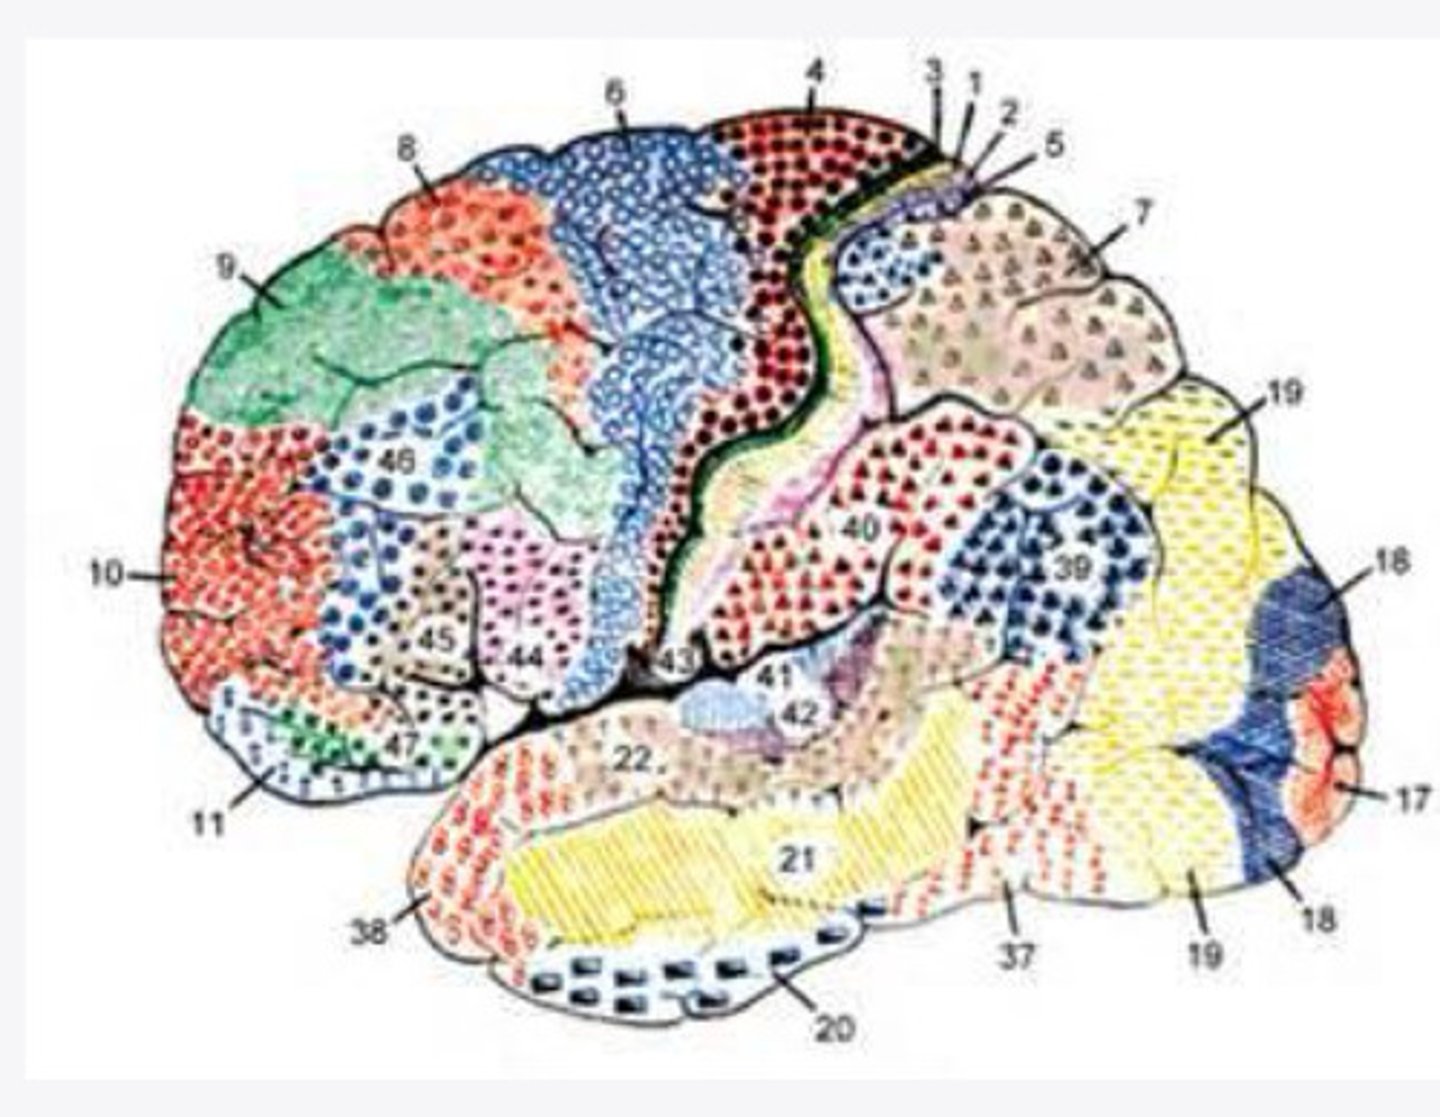

52 Brodmann areas

What are the histological divisions of the cortex of the brain?

cerebral cortex on the basis of histological sections

What did Brodmann study?

52 distinct regions of the cortex based on the thickness of cell layers alone

What did Brodmann find?

2-5

What layers of the cortex of the brain did Brodmann find were variable in histological sections?

function

In the 52 Brodmann areas, structure lens itself to ______

4, 6, 8, 44/45

What are the important Brodmann areas of the frontal lobe?

motor movements

What is the function of Brodmann area 4?

2 and 5

What layers of the cortex are thick in Brodmann area 4?

helps coordinate activity in the motor cortex (opposing muscle groups)

What is the function of Brodmann area 6?

2 and 3

What layers of the cortex are thick in Brodmann area 6?